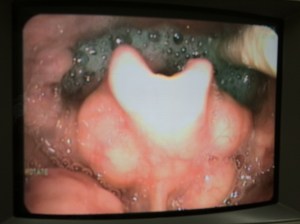

Oral motor impairment presents a variety of challenges for both the individual affected, and for the care team providing intervention. Often the individual experiencing oral motor difficulties is not able to follow commands. The person may not be eating or taking fluids orally, which reduces the opportunities for observation of oral movement patterns. The majority of baseline protocols currently available require at least minimal direction-following skills. The protocol developed by Beckman uses mechanical muscle responses, which are not mediated cognitively, to baseline the response to pressure and movement, range of movement, variety of movement, strength of movement and control of movement for the lips, cheeks, jaw, and tongue. In this two day course, participants will actively participate in hands-on practice for compensatory handling techniques for the following concerns: tonic bite, tonic bite on a utensil, slow oral transit, tongue thrust, cough, gag and vomit. The participants will complete an oral motor protocol with each other, analyze the results, and discuss data tracking. The participants will also complete hands-on practice for specific oral motor interventions to address the deficit areas discovered during baseline assessment. Additional topics of discussion may include: goal writing, diet texture progression, tube to oral issues, adaptive mealtime utensils, oral hygiene issues, medication administration issues, oral function for individuals with tracheotomy, facilitating improved articulation through oral motor techniques, research issues, videofluroscopy issues for motorically involved individuals.